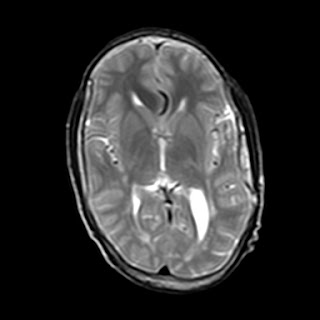

MRI of brain images: